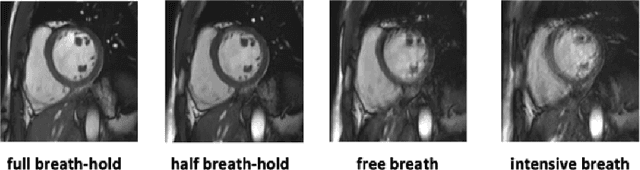

Methods that are resilient to artifacts in the cardiac magnetic resonance imaging (MRI) while performing ventricle segmentation, are crucial for ensuring quality in structural and functional analysis of those tissues. While there has been significant efforts on improving the quality of the algorithms, few works have tackled the harm that the artifacts generate in the predictions. In this work, we study fine tuning of pretrained networks to improve the resilience of previous methods to these artifacts. In our proposed method, we adopted the extensive usage of data augmentations that mimic those artifacts. The results significantly improved the baseline segmentations (up to 0.06 Dice score, and 4mm Hausdorff distance improvement).